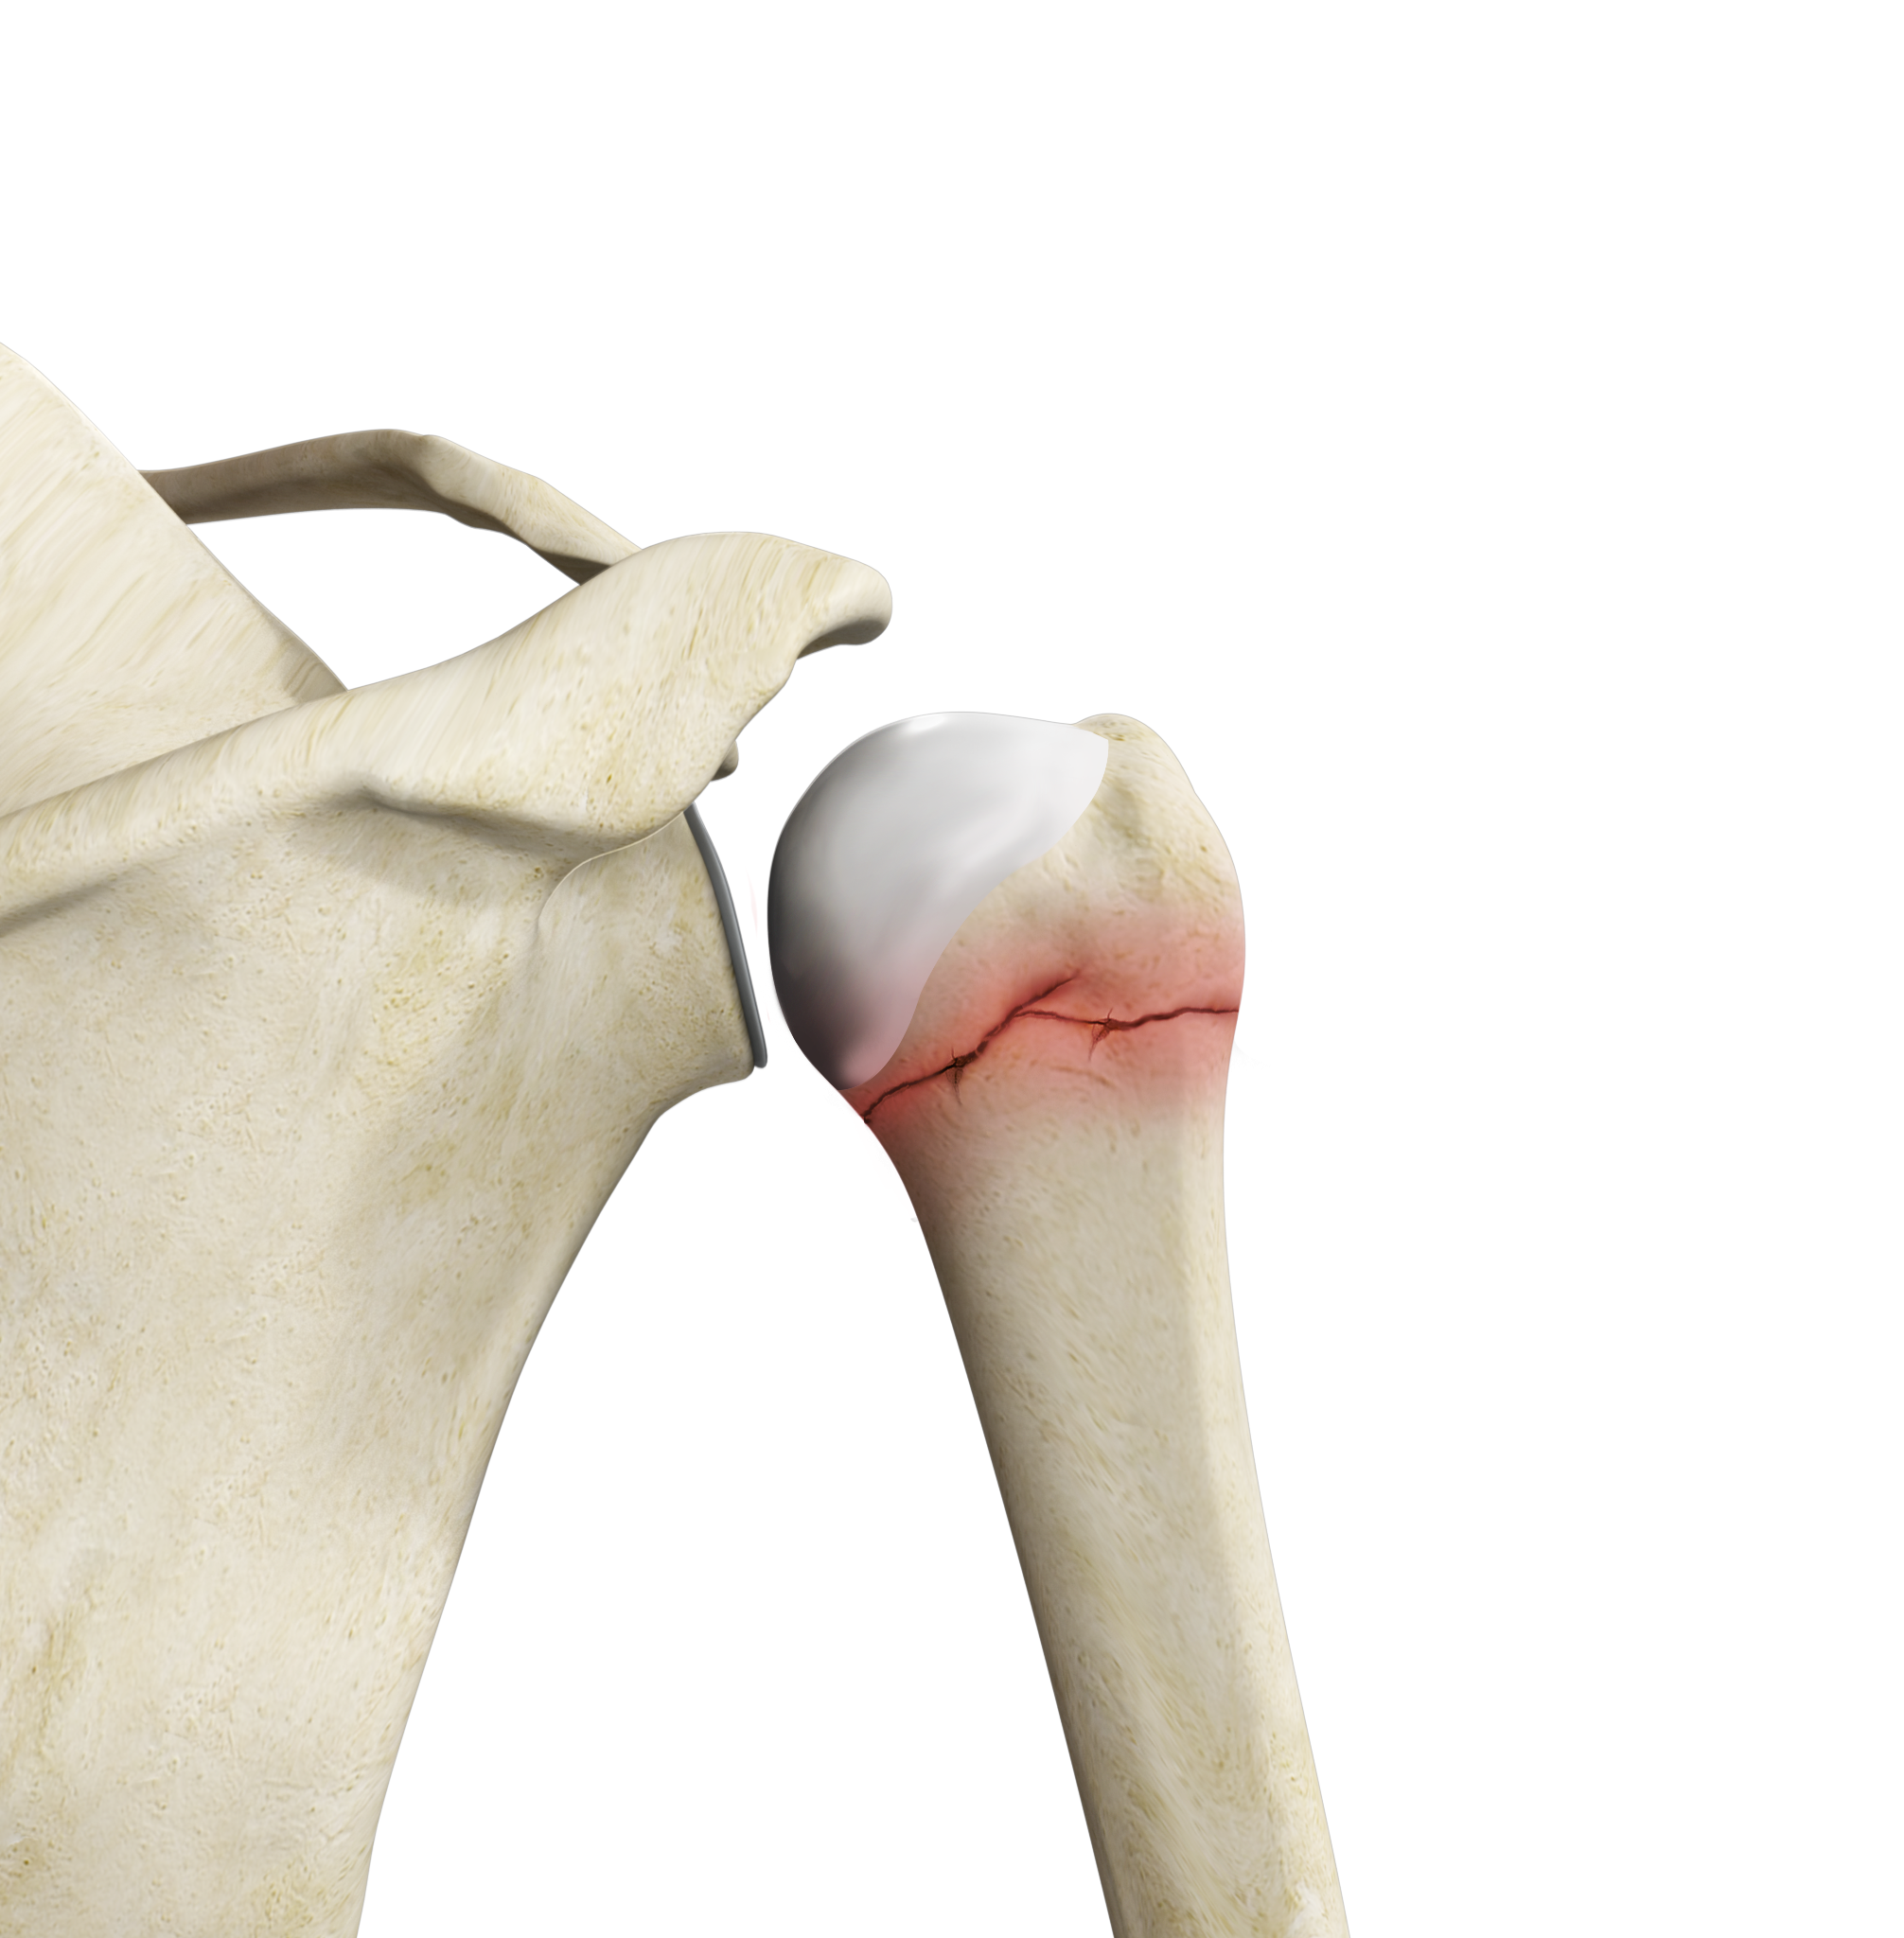

ORIF Proximal Humerus Fracture

Open reduction and internal fixation (ORIF) is a surgical technique employed for the treatment of fractures to restore the normal anatomy of the bone.

Proximal Humerus Fractures

Fractures of the proximal humerus are common in elderly individuals suffering from osteoporosis.